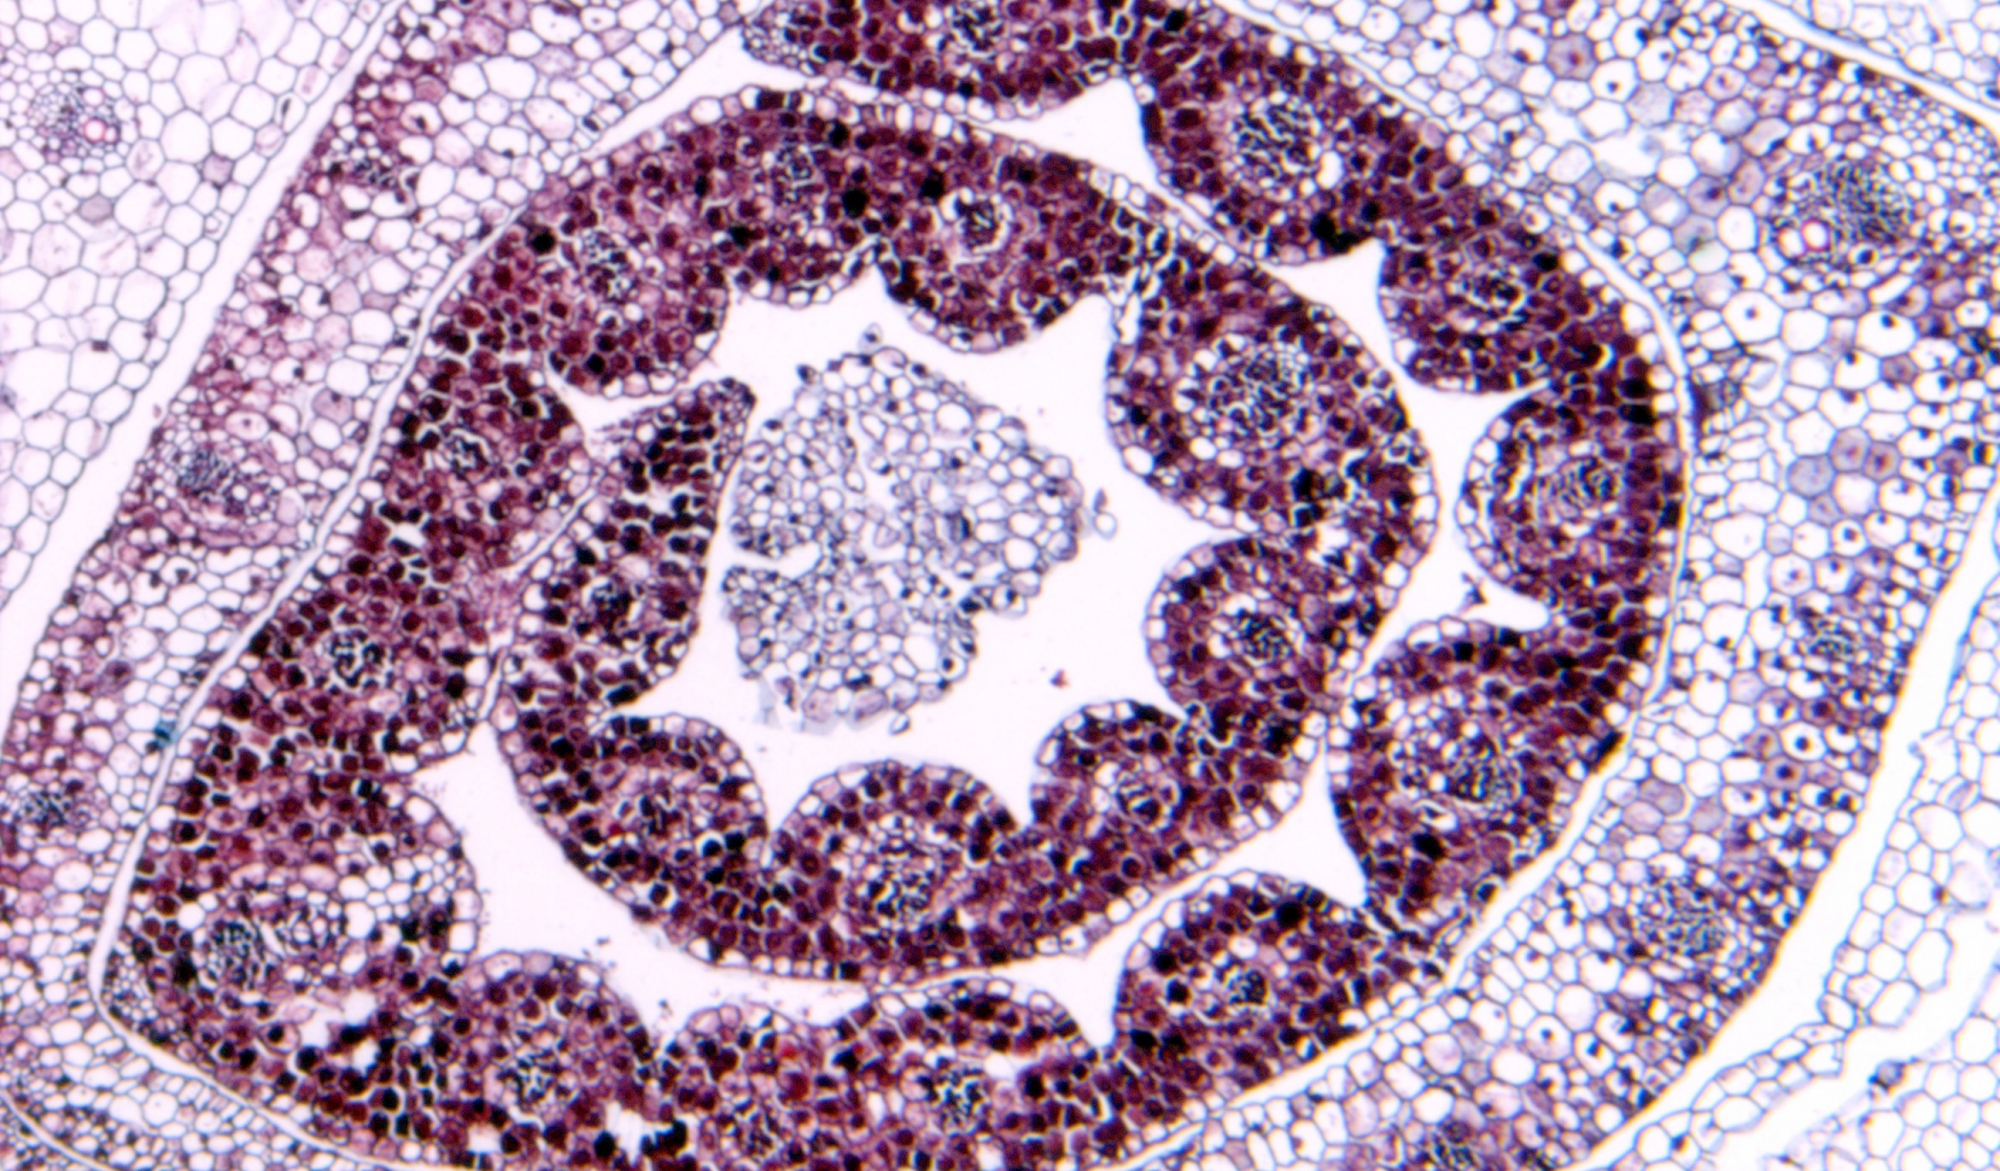

病理平臺(tái)可承接:石蠟切片,切片掃描,熒光掃描,HE染色,各種特殊染色,如:Masson、油紅O、PAS、番紅O、ALP、TRAP、甲苯胺藍(lán)以及免疫組化/熒光、原位雜交等,3D HISTECH滿足對(duì)結(jié)果高質(zhì)量,高標(biāo)準(zhǔn),周期快的實(shí)驗(yàn)外包需求,并提供染色培訓(xùn)服務(wù),分線上視頻,線下實(shí)操帶教兩種培訓(xùn)方案。

案例展示

組織染色實(shí)驗(yàn)室